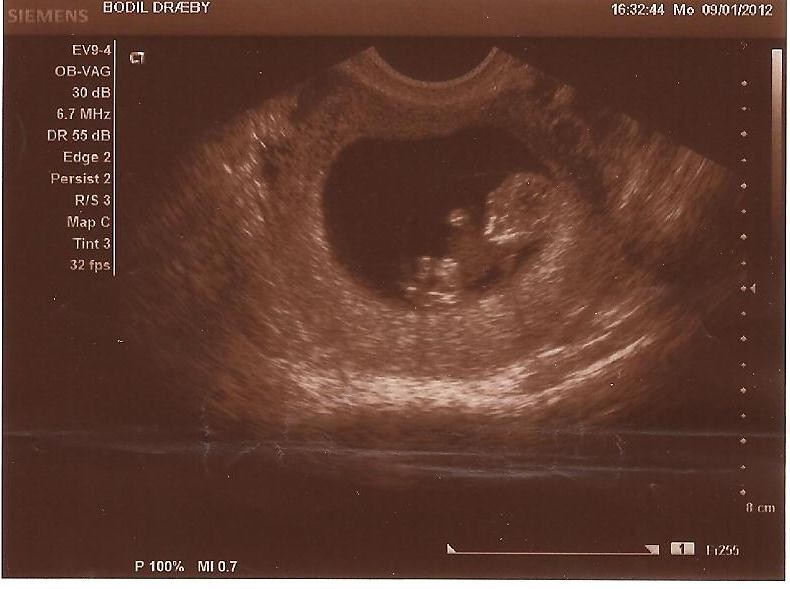

Jeg var til udvendig scanning 7+6, der kunne man se alt hvad man skulle se.

Den læge, der scannede mig, sagde det slet ikke var nødvendigt med indvendig scanning, men han er altså også meget erfaren.